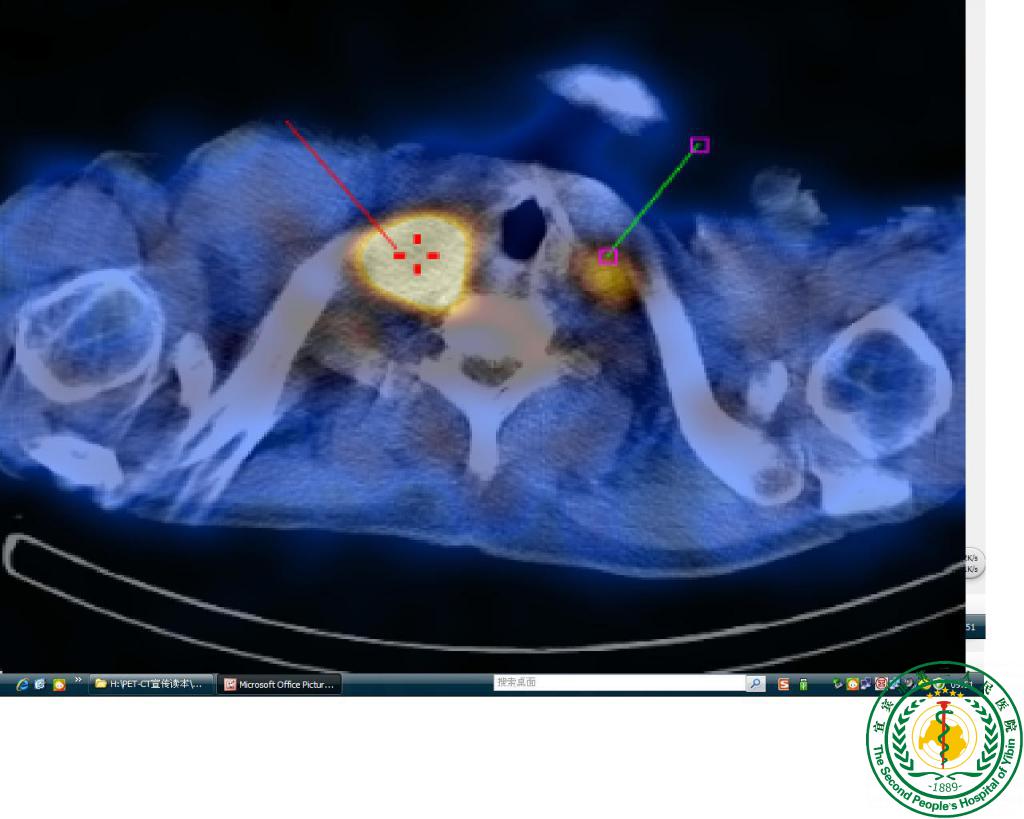

“鹰眼”派特CT确诊疑难“肺结节”一例

宜宾市第二人民医院 图文